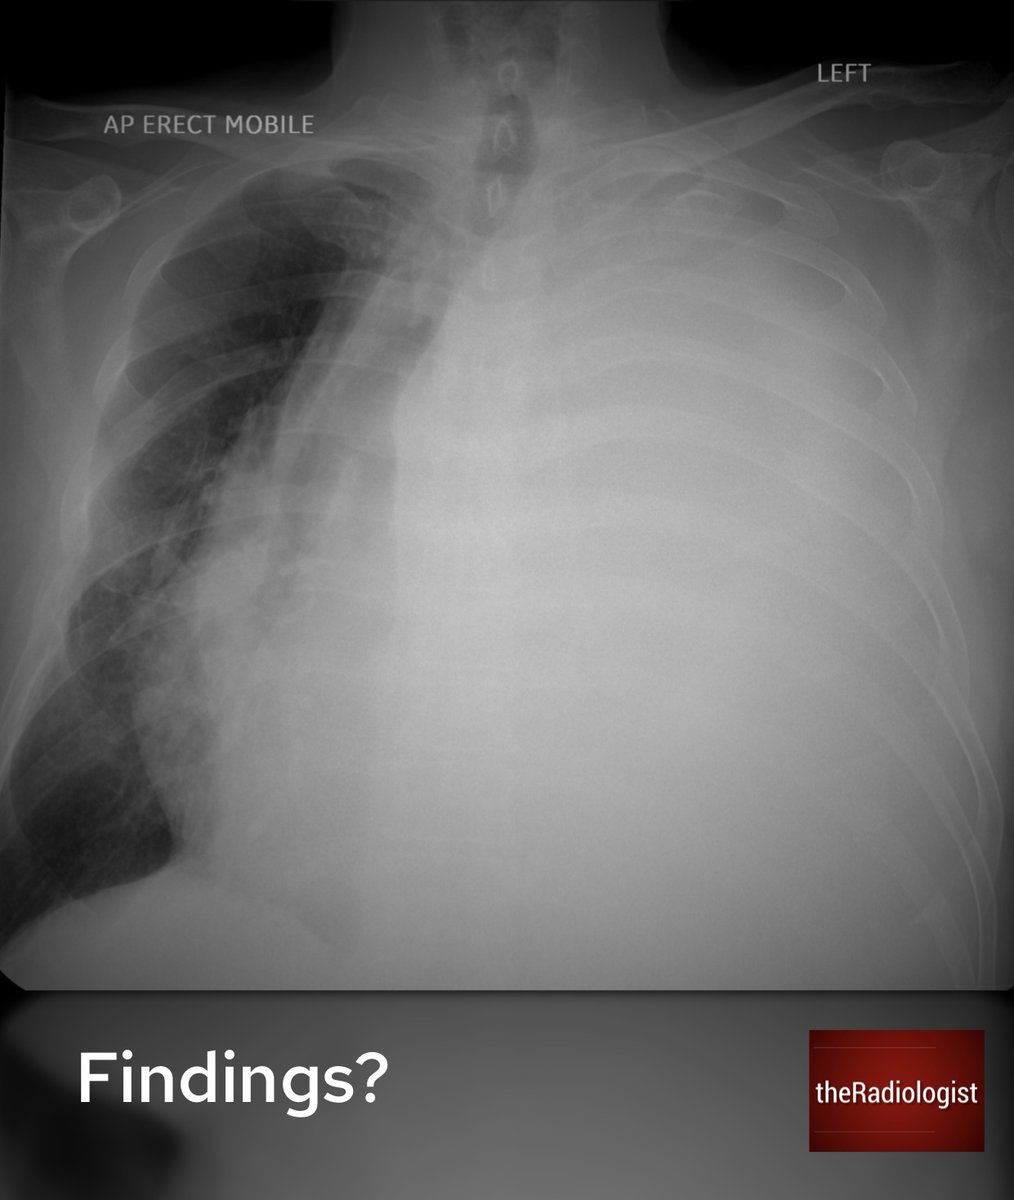

@DrCasteelEM @radiologistpage Mucus plug/atelectasis should not be on the differential. Wrong side shift